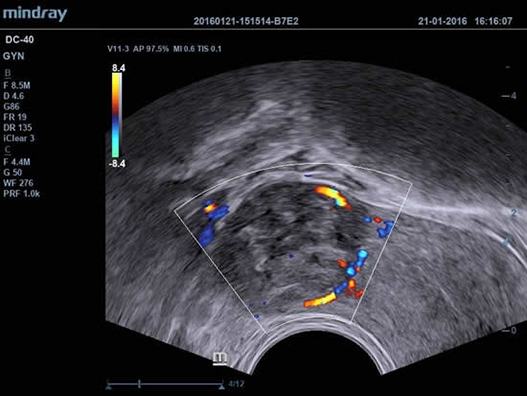

Mindray DC-40 - передовая УЗ-станция с выдающимися возможностями в области медицинской диагностики. Компания Mindray разработала это устройство с учетом высоких требований врачей к качеству изображения и быстродействию. DC-40 обеспечивает высокое качество изображения и точность диагностики, что является необходимым в повседневной практике врачей. Технологии, применяемые в этом устройстве, позволяют получать четкое и детализированное изображение.

Технологии iBeam, iClear и iScape, применяемые в DC-40, позволяют получать объемные изображения высокого качества без помех и зернистости в зоне сигнала. Панорамная визуализация с расширенным обзором анатомических структур решает проблемы сложных диагнозов, которые ранее создавали значительные трудности в ультразвуковой диагностике.

• Внутриполостной датчик Mindray V11-3